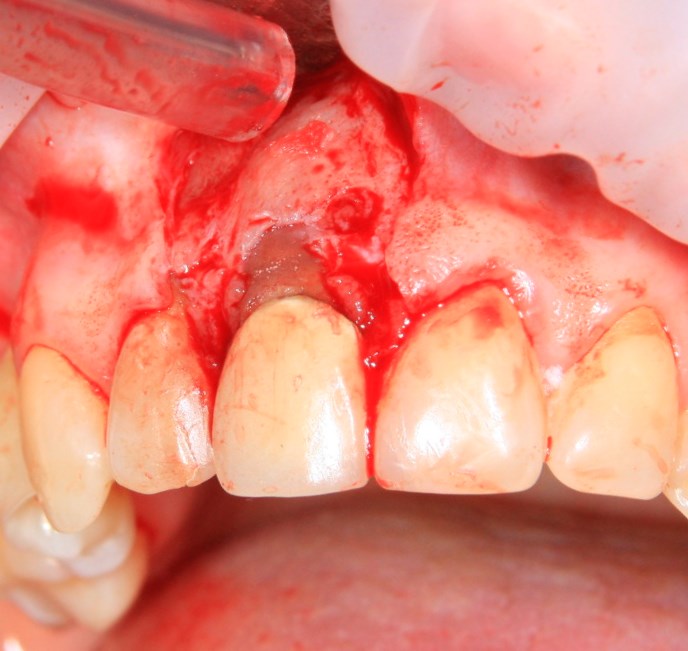

Немедленная имплантация — оптимальное решение в любой клинической ситуации